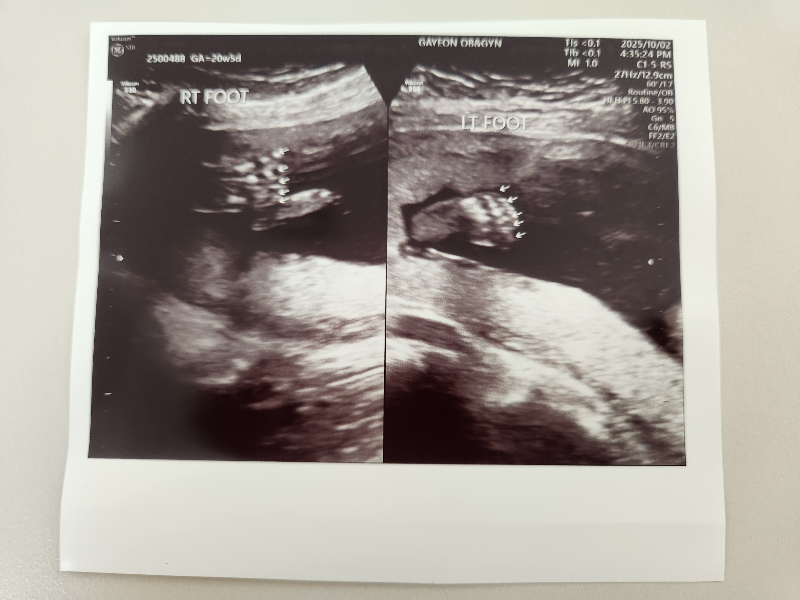

왼발 오른발 발가락을 확인합니다.